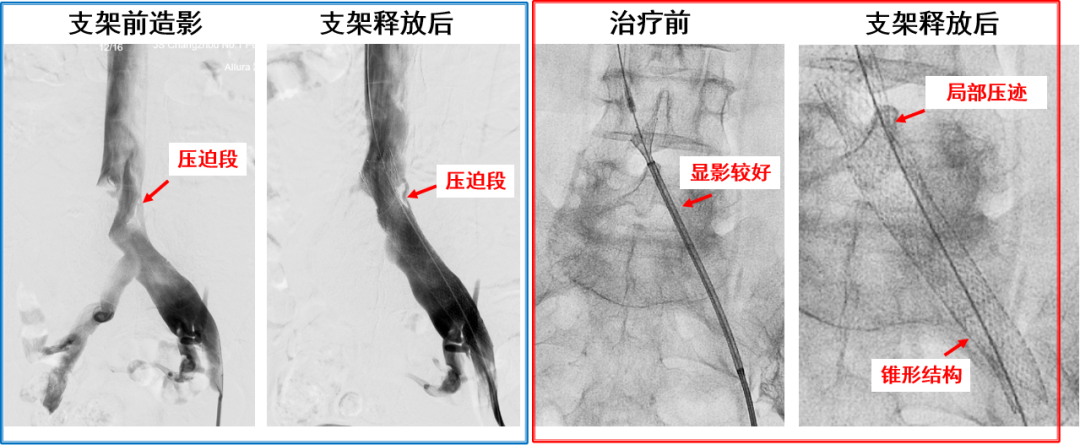

产品C:病例一(柔顺性及贴合性欠佳)

产品D:病例一(支撑力欠佳)

产品D:病例二(支架短缩)

优点:

封闭式无缝编织仿生支架,良好的柔顺性

贴合血管解剖结构和形态(“S”或“C”型走形)

近端锚定区直径加大,增加支撑力

支架近段可回收后再释放,增加成功率

整体支撑力一般

支架释放过程中出现短缩,较难把握